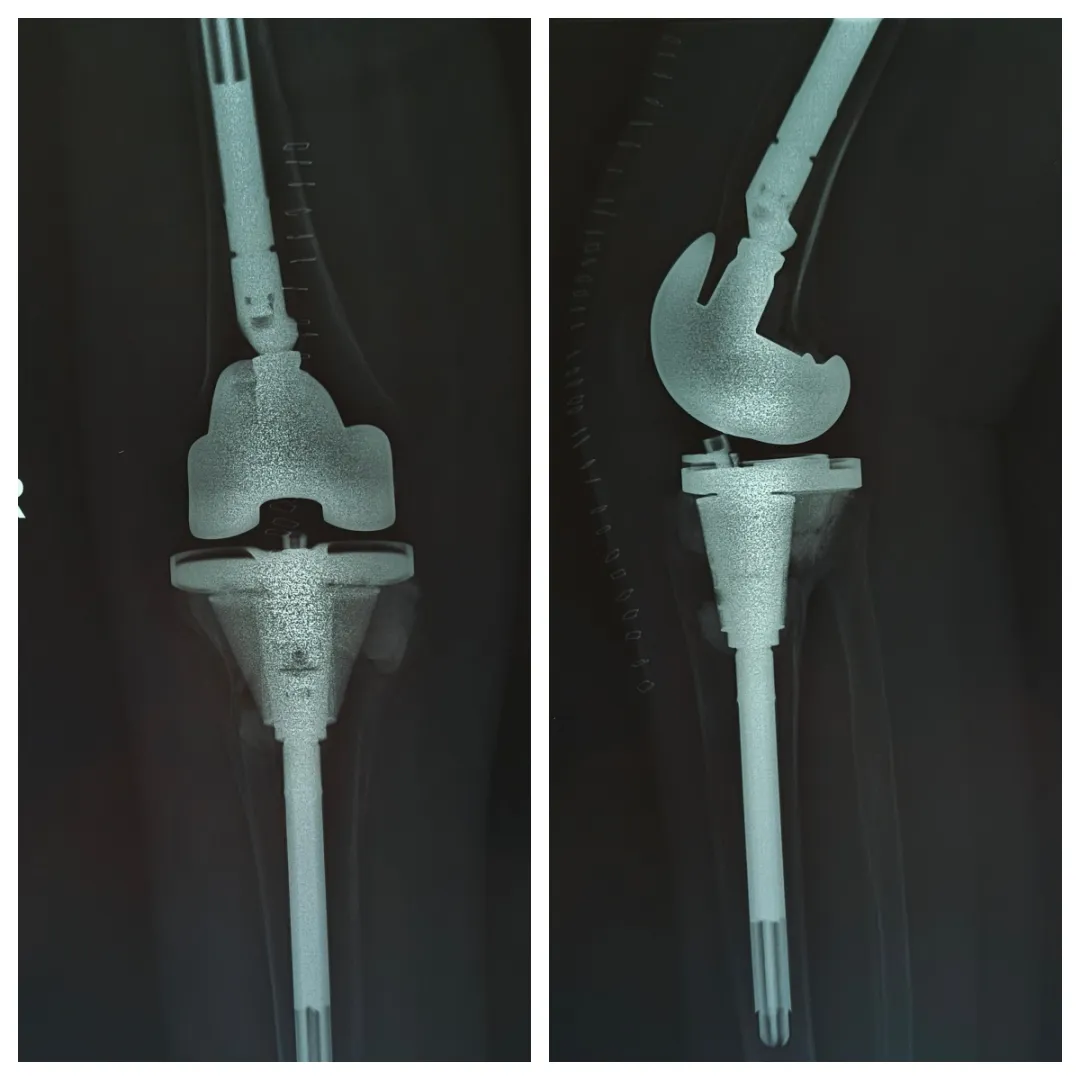

针对梁阿姨的病情,关节科团队制定了周密的手术方案。术中见其胫骨平台骨缺损严重,原有假体明显松动。团队采用

加长型膝关节翻修假体系统

,通过精准截骨、骨缺损重建、关节线恢复与软组织平衡等一系列高难度操作,顺利完成翻修。

术后X光显示,新假体位置良好,下肢力线恢复,关节稳定性重建。梁阿姨术后恢复顺利,已在医护人员指导下开始康复训练。